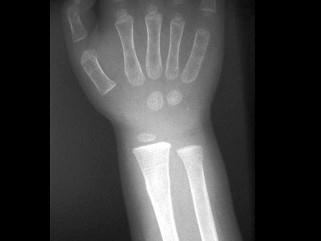

出生6个月的男婴,摔地后右手红肿,结合CR片,正确的骨折类型是?(?)A.青枝骨折B.横行骨折C.斜行骨折D.粉碎性骨折E.压缩骨折

问题 出生6个月的男婴,摔地后右手红肿,结合CR片,正确的骨折类型是?(?)

选项 A.青枝骨折 B.横行骨折 C.斜行骨折 D.粉碎性骨折 E.压缩骨折

答案 A